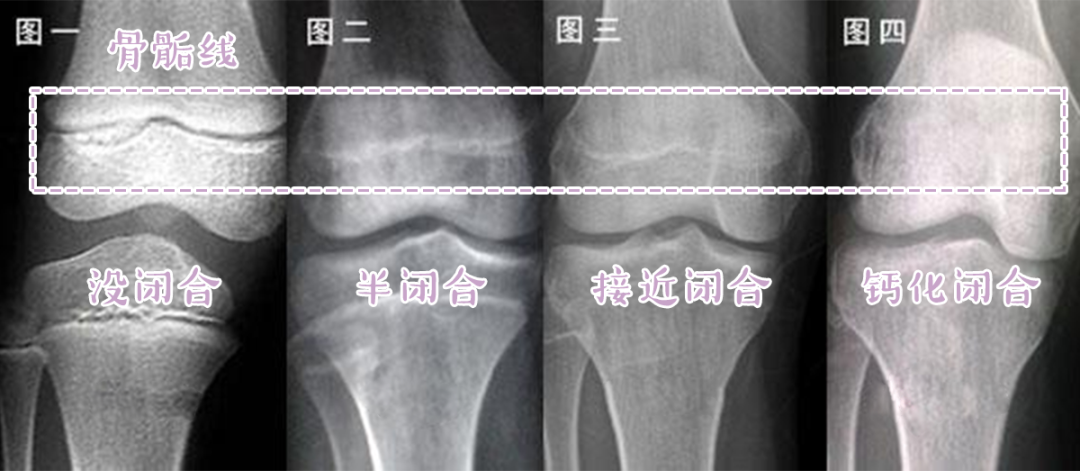

骨骺线闭合」也就是常说的这个结果我们就会停止生长等骺板彻底骨化后